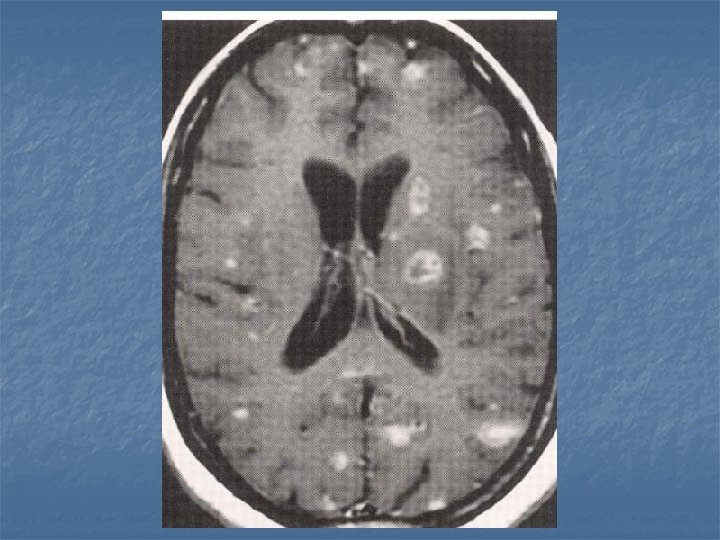

Toxoplasmosis n n n Yer kaplayan lezyonların % 60’ı % 30 olguda mevcut Kortikomedüller bileşke (? ), basal ganglion ve talamusda sık tutulum BT-MR. . . >5 lezyon, halka tarzında kontrast (+), nodüler, ödem ve kitle etkisi Erken tanı önemli. . . tedavi edilebilir 2 hafta primethamine+sulfadiazine